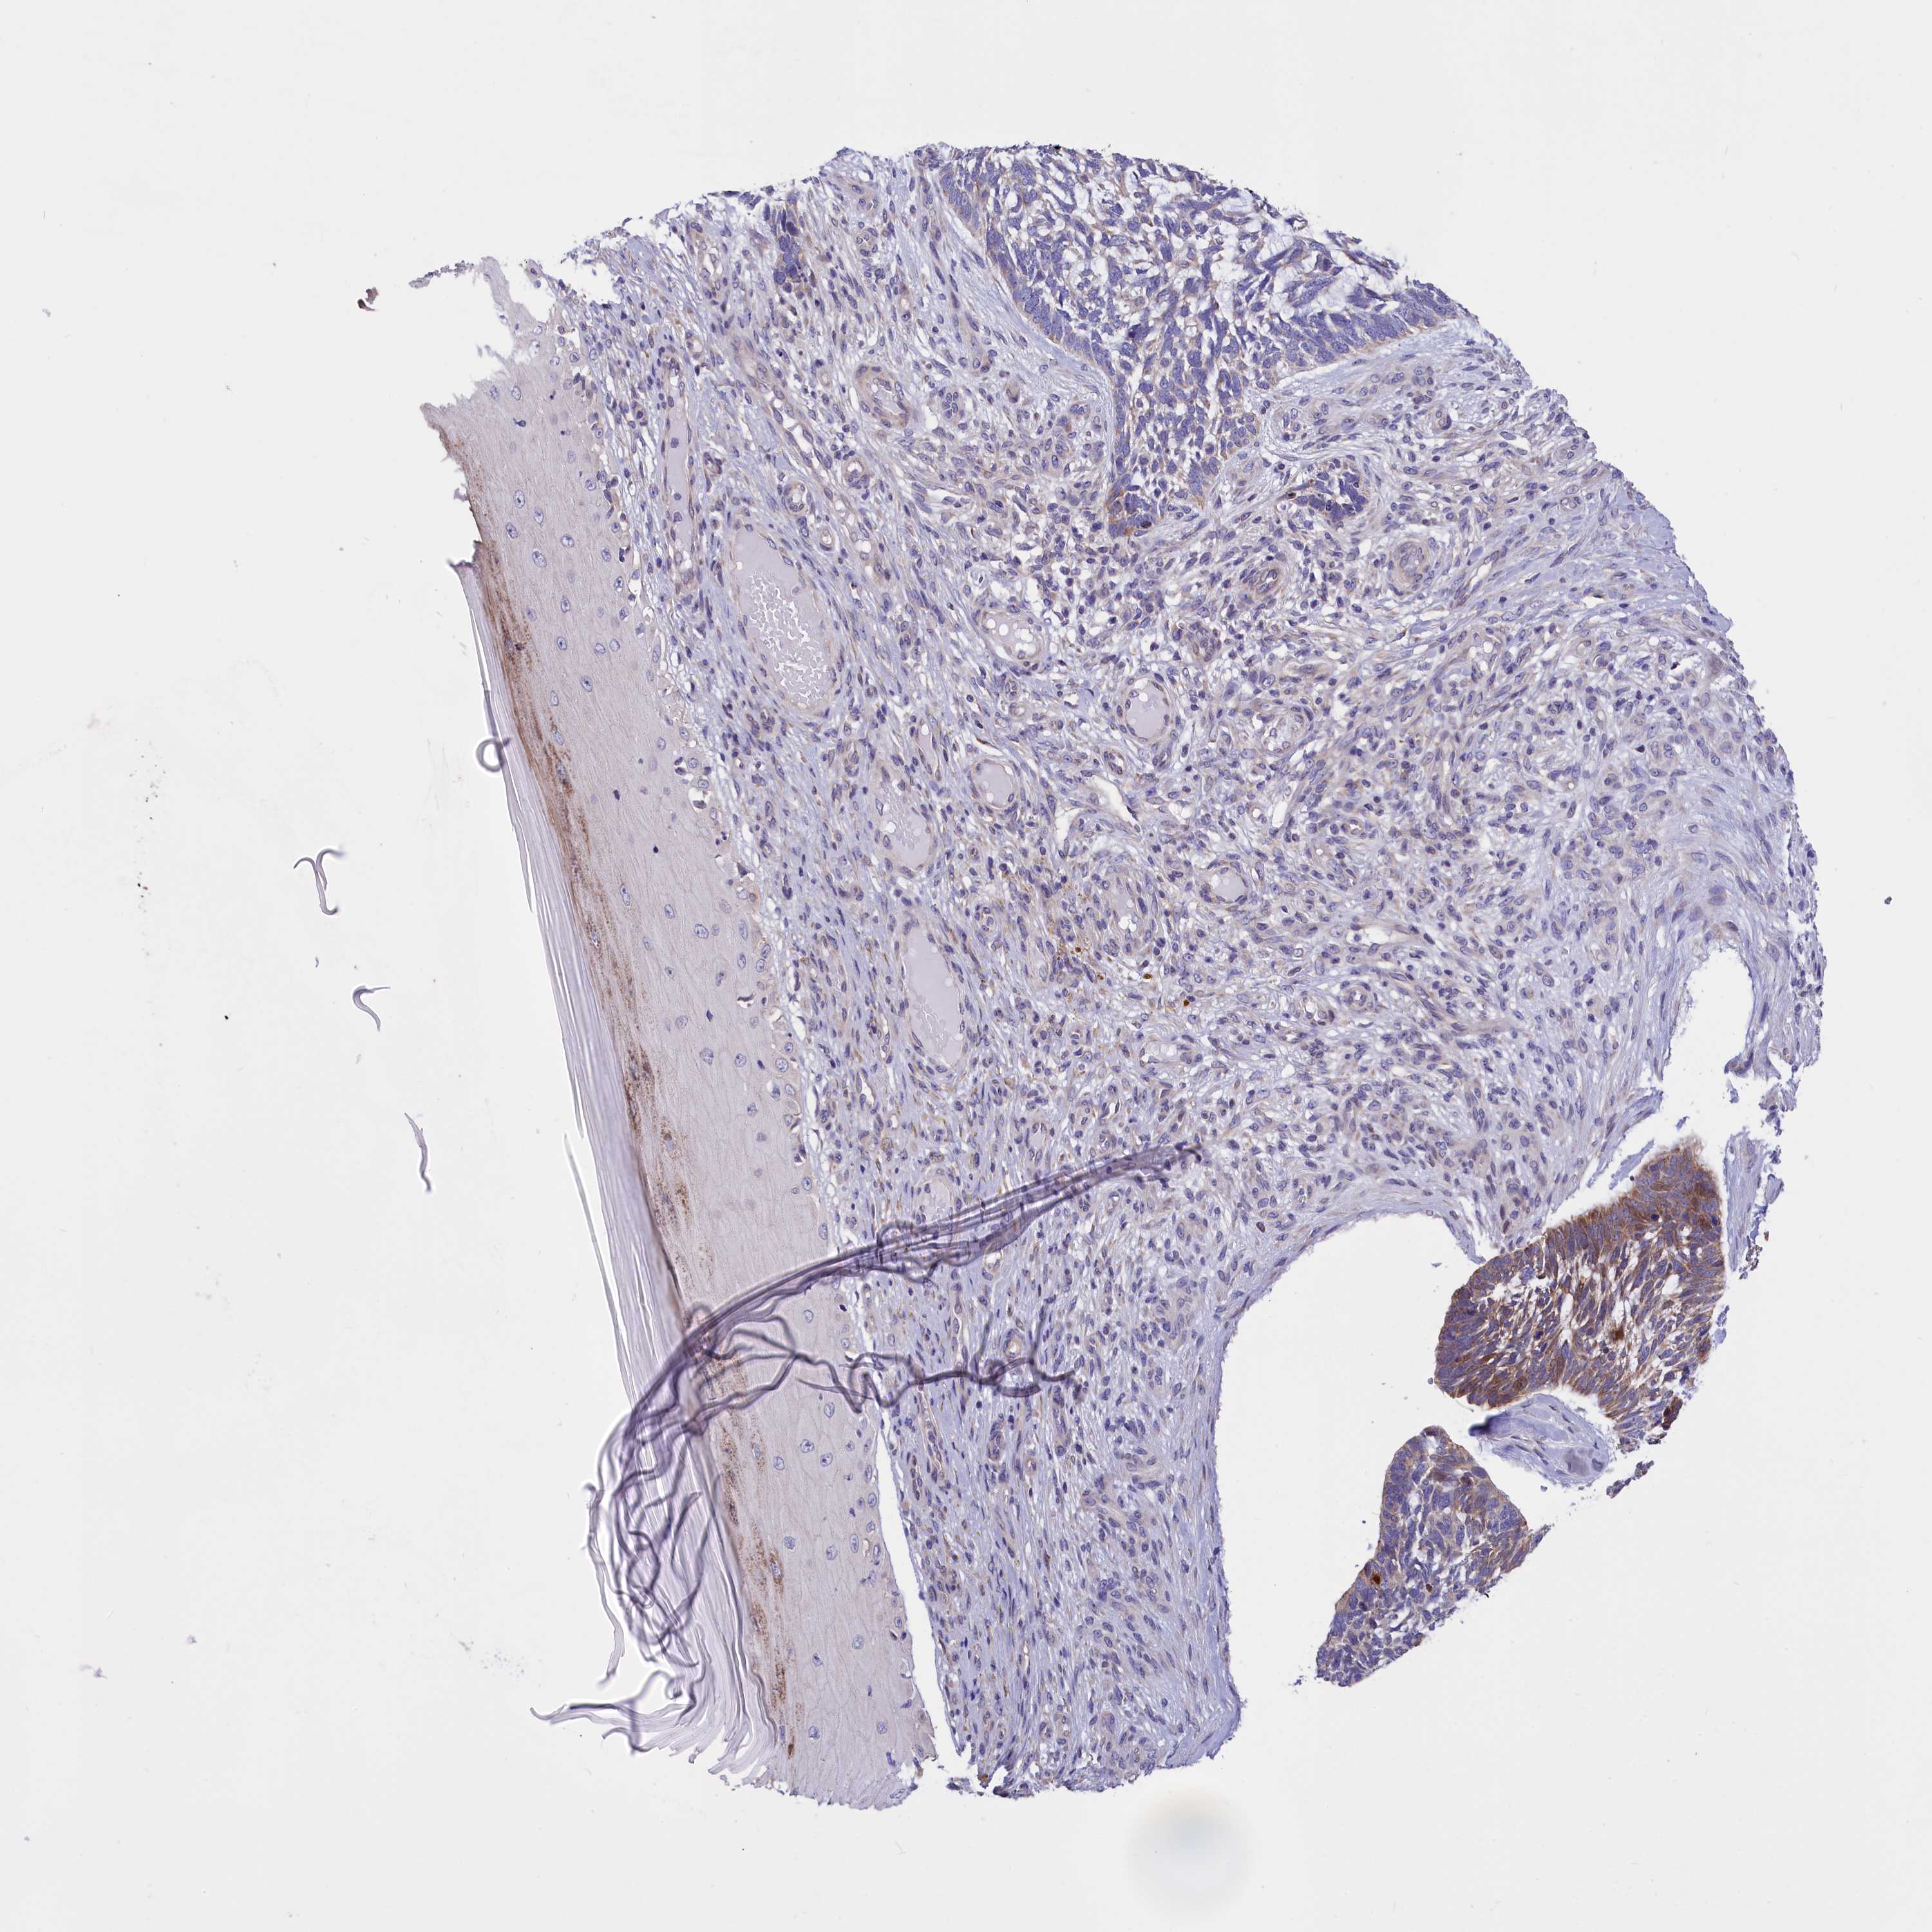

SKIN CANCER - Protein expressioni

A mouse-over function shows sample information and annotation data. Click on an image to view it in a full screen mode. Samples can be filtered based on level of antibody staining by selecting one or several of the following categories: high, medium, low and not detected. The assay and annotation is described here.

Each image is clickable and will lead to virtual microscopy that enables deeper exploration of all samples and also displays staining intensity scores, fraction scores and subcellular localization as well as patient and tissue information for each sample.

Antibody HPA046754

Staining

Medium

Strong

Moderate

75%-25%

Cytoplasmic/membranous

Squamous cell carcinoma, metastatic, NOS

Squamous cell carcinoma, NOS